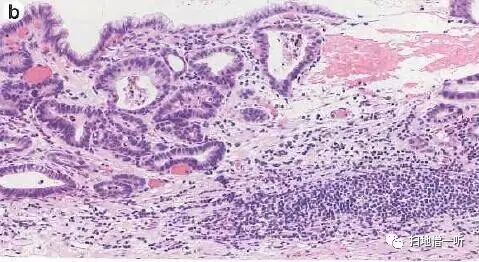

箭头处为自发出血处。高倍镜下可见高分化管状腺癌腺体。

最终病理诊断:

胃角小弯,O-IIc,2mm,tub1,T1a (M),UL(-)